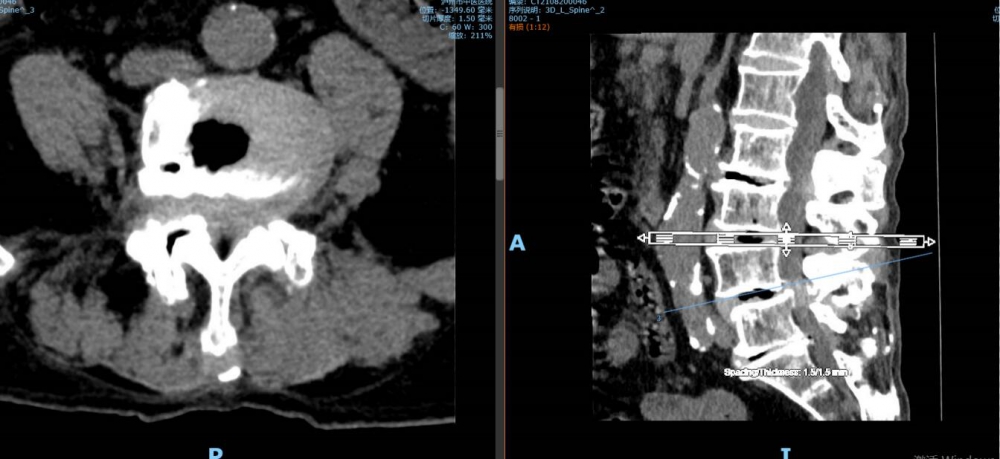

“我‘考試’去了,你們不要擔(dān)心”。8月27日上午8點,92歲高齡的李謹(jǐn)行老人被推進(jìn)了瀘州市中醫(yī)醫(yī)院的手術(shù)室,進(jìn)手術(shù)室前,老人樂觀地寬慰著兒女們。此番,醫(yī)生將為老人進(jìn)行骨科手術(shù),若手術(shù)成功,老人將結(jié)束幾乎癱瘓在床的日子;老人同時還患有腰椎管狹窄癥等17種疾病,這樣的情形下,無論是對老人的身體還是醫(yī)生而...